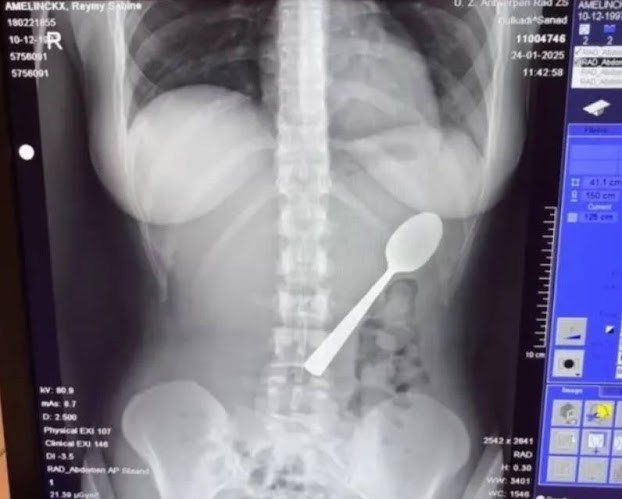

Hình ảnh chụp x-quang cho thấy chiếc thìa dài trong dạ dày của Reymy. Ảnh: Jam Press/VNE

Hình ảnh chụp X-quang sau đó cho thấy chiếc thìa nằm nguyên vẹn trong dạ dày của cô. Do kích thước quá lớn, các bác sĩ nhận định dị vật không thể tự đào thải qua đường tiêu hóa.